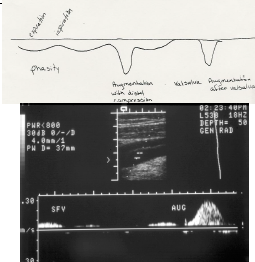

is this normal doppler? how can you tell?

Color should fill vessel. Flow toward head

what 5 things need to be present for a normal spectral appearance?

spontaneity

Phasity

Cessation with proximal compression or valsalva

Augmentation with distal compression

Non-pulsatile

respiration

deep inspiration stops flow

expiration augments

lack of phasity indicates obstruction proximal or systemic venous HTN, collateralization, “windstorm effect”

augmentation

patency of veins at and above compression site

lack of augmentation - thrombus of calf, at site or above

is this duplex normal or abnormal?

normal – 5 phases